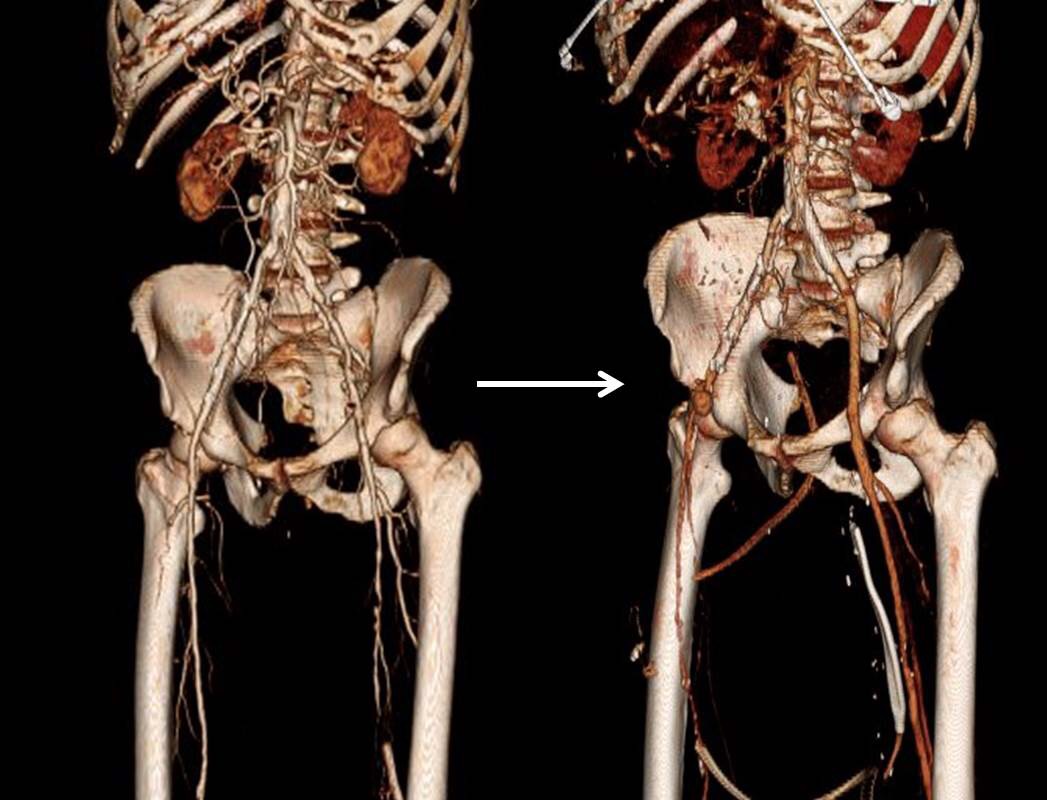

Let me show you one of the first cases I did after returning to Cleveland. I am now practicing at Fairview and Avon Hospitals, premier flagship hospitals in the Cleveland Clinic fleet, on Cleveland’s west side, and a patient arrived while I was on call with sudden onset of pain in his leg from a lack of blood flow. He had occlusive atherosclerotic plaque extending from his external iliac artery to the above knee popliteal artery causing ischemic rest pain.

I contacted LeMaitre Vascular and got in touch with your representative, L. Fisher, who promptly sent the Moll Ring Cutters I needed to perform a remote endarterectomy of the patient’s occlusive external iliac and superficial femoral artery plaque. The technical details of remote endarterectomy are have been covered in my blog (https://vascsurg.me/?s=endore), but in the end, through a 7cm incision in the groin (don’t believe the hype, this is minimally invasive), I restored his arteries to their original open condition. Shown below are the results. It was with great sadness that I heard that the LeMaitre Vascular equipment being sent were the last of the stock available in North America. The patient did very well, with the operation completed well before lunch, and is recovering rapidly from his small wound and big rescue. He gets to walk out of the hospital on two legs, but also with the surety that he avoided a major bypass operation, and avoided the short term gains of stenting from the aorta to the profunda -more peel packs and landfill items and a dubious long term durability. Hey, I even used a XenoSure patch on the common femoral.